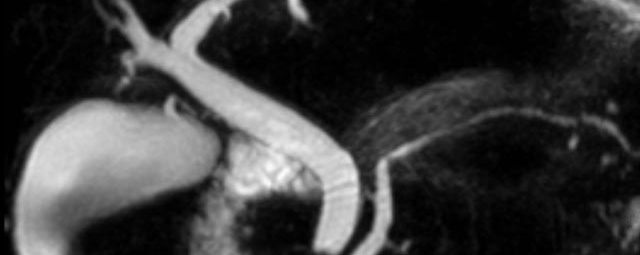

MR-Angiografie (MRA)

• MR-Angiografie ohne Kontrastmittel

• Time of Flight (TOF)-Angiographie

Je nach Fragestellung und Körperregion Gefäßdarstellung ohne Kontrastmittel bei Kontrastmittelunverträglichkeit oder terminaler Niereninsuffizienz möglich.

• MR-Angiographie mit Kontrastmittel

• Erfassung arterieller und venöser Gefäße/Bypässe aller Körperregionen mit 3D-Rekonstruktion

MR-Angiographie zur Erfassung und Verlaufskontrolle von Aneurysmen der Aorta thorakalis und ihrer Gefäßabgänge